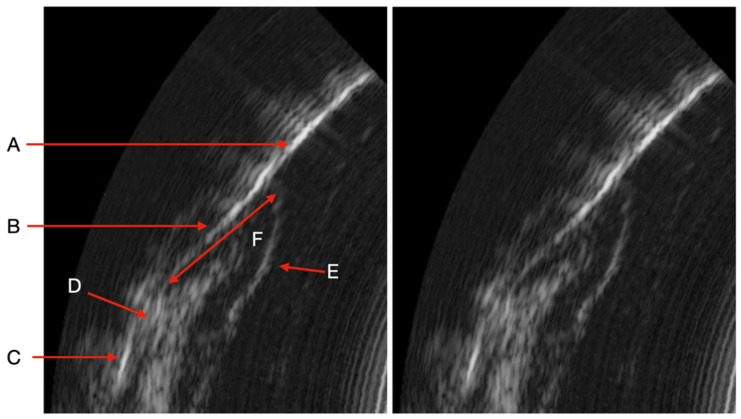

Objectives: This pilot study evaluates the correlation between periodontal pocket depth (PPD) measurements obtained by manual probing and those derived from an AI-coupled ultrasound imaging device in periodontitis patients. Materials and Methods: Thirteen patients with periodontitis underwent ultrasonic probing with an AI engine for automated PPD measurements, followed by routine manual probing. Results: A total of 2088 manual and 1987 AI-based PPD measurements were collected. The mean PPD was 4.2 mm (range: 2-8 mm) for manual probing and 4.5 mm (range: 2-9 mm) for AI-based ultrasound, with a Pearson correlation coefficient of 0.68 (95% CI: 0.62-0.73). Discrepancies were noted in cases with inflammation or calculus. AI struggled to differentiate pocket depths in complex clinical scenarios. Discussion: Ultrasound imaging offers non-invasive, real-time visualization of periodontal structures, but AI accuracy requires further training to address image artifacts and clinical variability. Conclusions: The ultrasound device shows promise for non-invasive periodontal diagnostics but is not yet a direct alternative to manual probing. Further AI optimization and validation are needed. Clinical Relevance: This technology could enhance patient comfort and enable frequent monitoring, pending improvements in AI reliability.